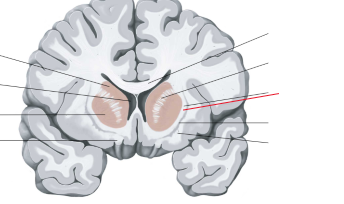

nucleus caudatus

putamen

globus pallidus

capsula interna (corona radiata)

capsula externa

capsula extrema

laterale ventrikels (I en II)

septum pellucidum